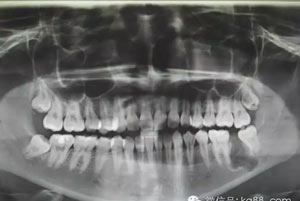

圖1.術(shù)前患者的全景片影像檢查情況:37未萌出,牙冠周圍有囊性陰影,牙根接近下頜骨皮質(zhì)骨邊緣。

1.jpg